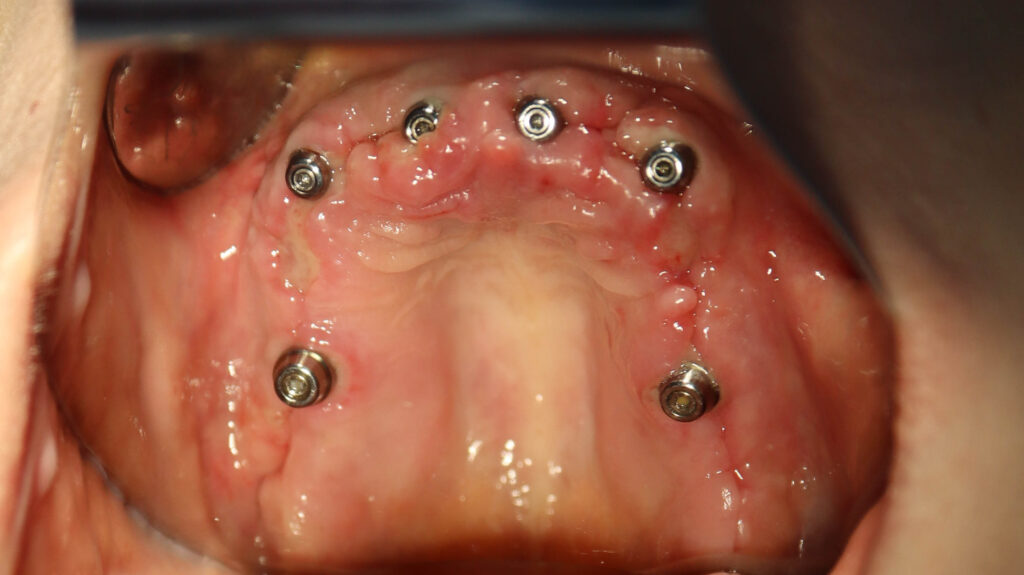

На верхней челюсти были удалены зубы, которые находились в неудовлетворительном состоянии, проведена комплексная имплантация по системе All-on-6, установлены 4 имплантата Megagen AnyOne и 2 скуловых имплантата NeoDent.

Спустя 7 дней на верхней челюсти зафиксирован металлоакриловый протез из 12 зубов.

результаты

Установлен условно-съемый металлоакриловый протез на 12 зубов